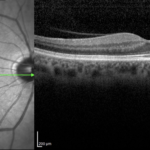

Varice della vena vorticosa: meno dell’1% fra gli pseudomelanomi